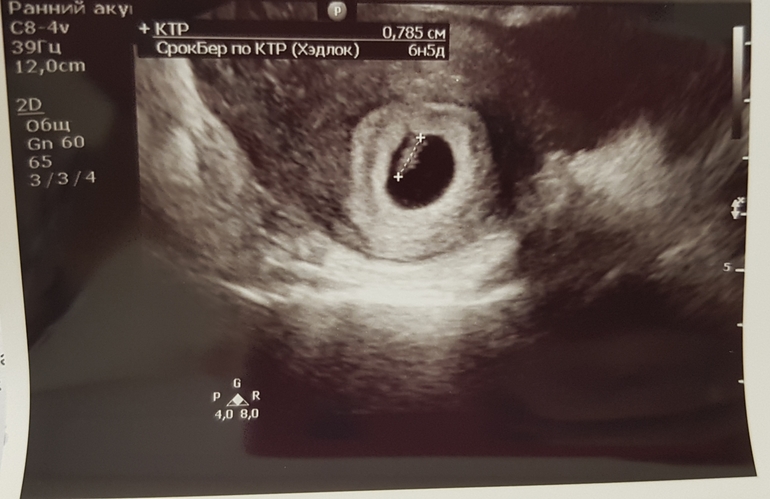

Узи 6нед 5 дн

Сегодня была на узи, где увидели нашу креветочку и дали послушать сердечко (КТР 8 мм, сб 132 удара/мин.), это незабываемо!!! До этой стадии я никогда не доходила, все время либо В либо ЗБ были, а тут включили на аппарате сердечко послушать и я просто в шоке до сих пор, поверить не могу, что все со мной происходит и что у меня внутри маленький, но такой важный чУловечек живет))))